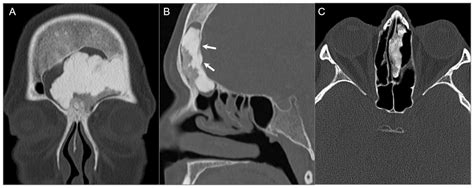

The skull base is a dense, bony platform that houses the brain. A Skull Base Tumor occurs when abnormal cells begin to divide uncontrollably in this anatomical region. These tumors are categorized based on their location, which is generally divided into three sections: the anterior (front), middle, and posterior (back) skull base. Depending on their origin, these growths can impact the eyes, nose, throat, or inner ear.

To confirm the presence of a tumor, specialists typically employ a variety of advanced imaging techniques. A standard physical examination is often followed by specialized diagnostic tests to map the extent of the tumor:

CT Scan (Computed Tomography) Highly effective at highlighting bony structures and identifying tumor-related bone erosion.